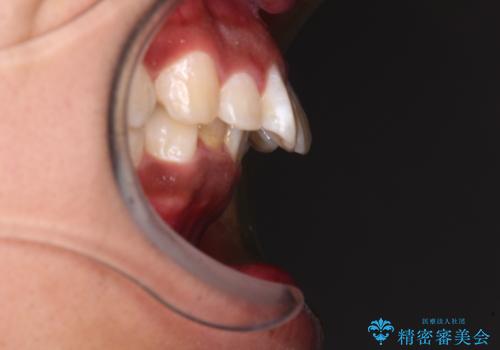

口元の突出感はあまりありませんでしたが、上顎歯列が全体的に前方にあり、更には下顎歯列が深く咬みこんでいるために、上顎前歯が前方に突出している状態でした。

抜歯は行わず、補助装置を用いて上顎歯列全体を後方移動させ、ワイヤー装置にて奥歯の咬み合わせを改善していくこととしました。